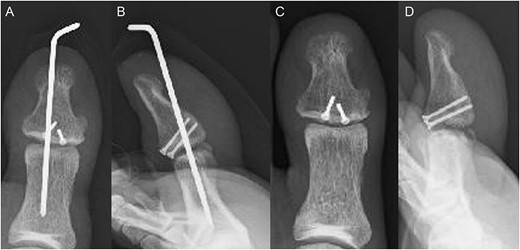

A 54-year-old man injured his right great toe while walking and wearing sandals. He complained of tenderness, swelling, and pain during motion. He could bear weight but could not actively extend the interphalangeal (IP) joint of the hallux. He was referred to our outpatient clinic 3 days after the injury. Physical examination revealed swelling, tenderness, and motion pain, and the patient could not extend the IP joint of the hallux. Plain lateral radiography and computed tomography revealed a displaced avulsion fracture of the dorsal base of the distal phalanx (Fig. 1). Surgery was performed under general anesthesia after informed consent was obtained on posttraumatic day 11. A Y-shaped incision was made at the center of the dorsal IP joint, and the displaced bony fragment was attached to the extensor hallucis longus (EHL). The IP joint was temporarily fixed with a 1.6 mm Kirschner wire, and the fragment was repositioned and fixed with two 1.5 mm cortical screws (APTUS® Hand, Medartis, Basel, Switzerland). A 4-0 FiberWire® (Arthrex, Naples, FL, USA) was fastened as an augmentation proximally to the EHL tendon and distally to the periosteum of the distal phalanx in a figure eight (Fig. 2). Postoperatively, the ankle was externally fixed in dorsiflexion from the leg to the toe, and heel loading was permitted. A total of 4 weeks after surgery, the Kirschner wire was removed to allow active motion of the IP joint of the hallux, and weight bearing was allowed on the hallux 5 weeks postoperatively. Plain radiographs taken 3 months after surgery confirmed bone healing (Fig. 3). A total of 20 months postoperatively, the patient acquired normal function, and the range of motion of the affected IP joint ranged from −3° to 30°, with no difference from the unaffected side (Fig. 4). Skin necrosis or nail deformities were not observed.

Physical findings 20 months after surgery (A) show EHL relief. Active motion shows IP joint range from (B) –3 to (C) 30°.